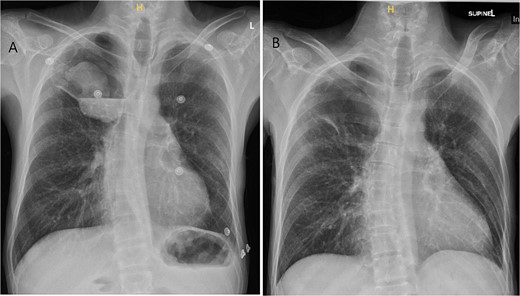

CT imaging of right intracavitary lung mass found within the wall of a longstanding bulla, along with heterogeneous fluid layering within the cavity (A). The mass was reported to be 4.4 × 5.2 cm and was concerning for primary bronchogenic malignancy. This lesion increased to 6.8 × 5.9 cm, demonstrating intense increased FDG activity and interval increase in fluid layering within the bulla within 2 months on follow-up PET imaging (B).

A PET scan done 2 months after the original CT scan showed that the lesion had increased in size (3.3 × 6.8 × 5.9 cm compared to previous CT findings of 2.7 × 3.9 cm), and demonstrated intense increased fludeoxyglucose (FDG) activity, with several smaller foci of similar intense grade FDG avid soft tissue nodules along the posterior aspect of the inferior bulla (Fig. 2). There was also an interval increase in fluid layering within the bulla. There was no distant metastasis.